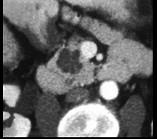

患者,女,57岁,上腹部隐痛半年余,CT片,最可能的诊断是 ( )A.胰腺癌B.胰腺脓肿C.胰腺假性囊肿D.胰腺囊腺瘤E.胰岛细胞瘤

问题 患者,女,57岁,上腹部隐痛半年余,CT片,最可能的诊断是 ( )

选项 A.胰腺癌 B.胰腺脓肿 C.胰腺假性囊肿 D.胰腺囊腺瘤 E.胰岛细胞瘤

答案 D